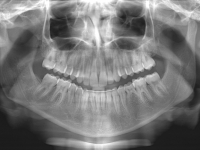

Premolar mandibular incluido + fenestración

45 incluido

Radiografía de final de tratamiento